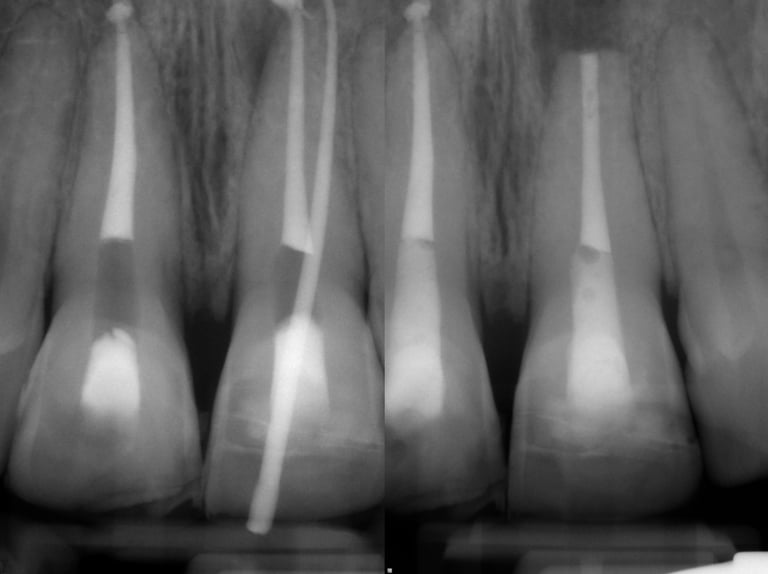

Gallery 3: Surgical Cases

Surgical Root Canal Cases (Apicoectomy) with preoperative and postoperative radiographs.

#3 Sx MB Root

#13 Sx

#14 Resurgery MB & DB roots

#10 Sx

#9 Sx